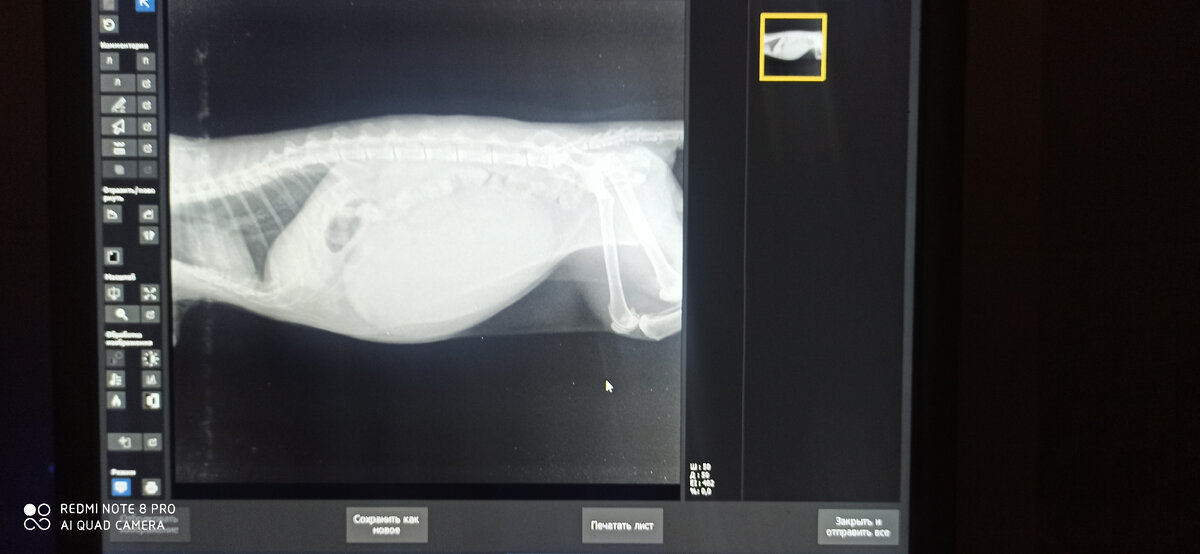

Сложно поверить, но это действительно так, мы сделали коту рентген и на нём красовался огромный мочевой, занимающий почти всю брюшную полость.

Питомца забрали на стационар, отводили мочу, делали анализы, узи, к всему общему удивлению почки ещё не плохо справлялись со своей функцией, не смотря на растянутый, переполненный мочевой и уже позже обнаружившееся новообразование левой почки.

У Сени нейрогенный мочевой пузырь.